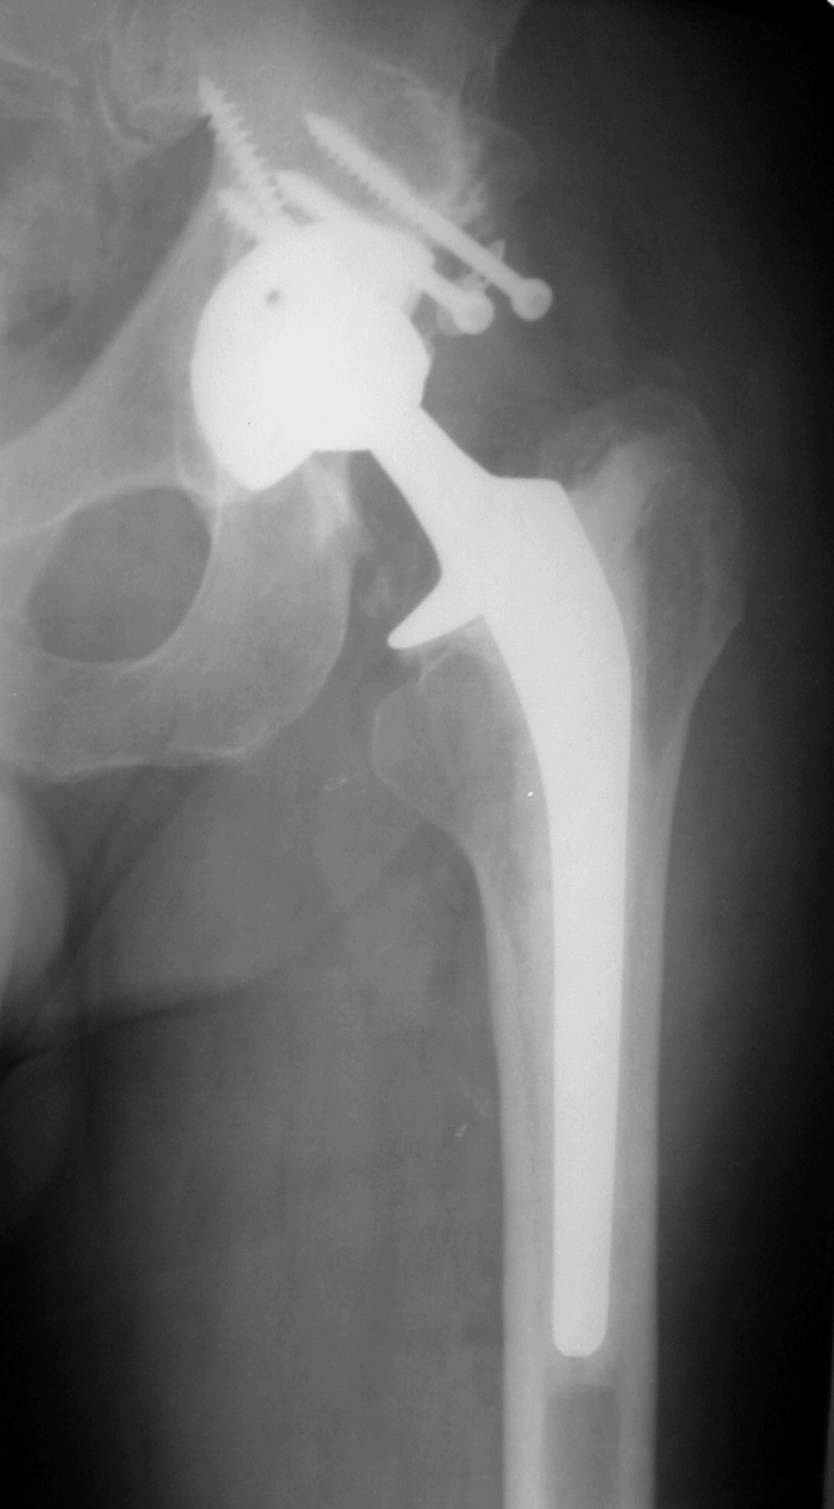

В институте совместно с фирмой Зиммер достаточно регулярно (практически ежемесячно) проводятся 2-х недельные циклы по различным вопросам эндопротезирования. Если есть возможность и желание, мы готовы поделиться с Вами нашим опытом, тем более есть что показать и что обсудить - в настоящее время ежедневно выполняется от 6 до 10 эндопротезирований коленного и тазобедренного сустава. В качестве примеров хочу показать 2 наблюдения, через 1 год и 5 лет после операции

5 лет